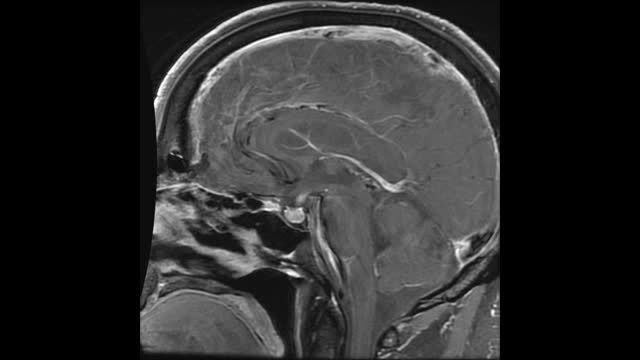

35-year-old lady presents with AGMA, AMS, Dizziness, Ataxia, Slurred Speech.